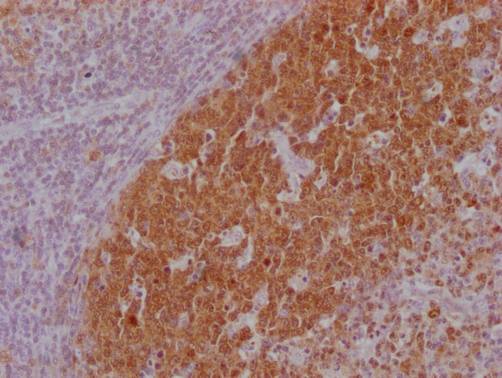

IHC image of CSB-MA181399 diluted at 1:100 and staining in paraffin-embedded human lymph node tissue performed on a Leica BondTM system. After dewaxing and hydration, antigen retrieval was mediated by high pressure in a citrate buffer (pH 6.0). Section was blocked with 10% normal goat serum 30min at RT. Then primary antibody (1% BSA) was incubated at 4°C overnight. The primary is detected by a Goat anti-mouse IgG polymer labeled by HRP and visualized using 0.05% DAB.